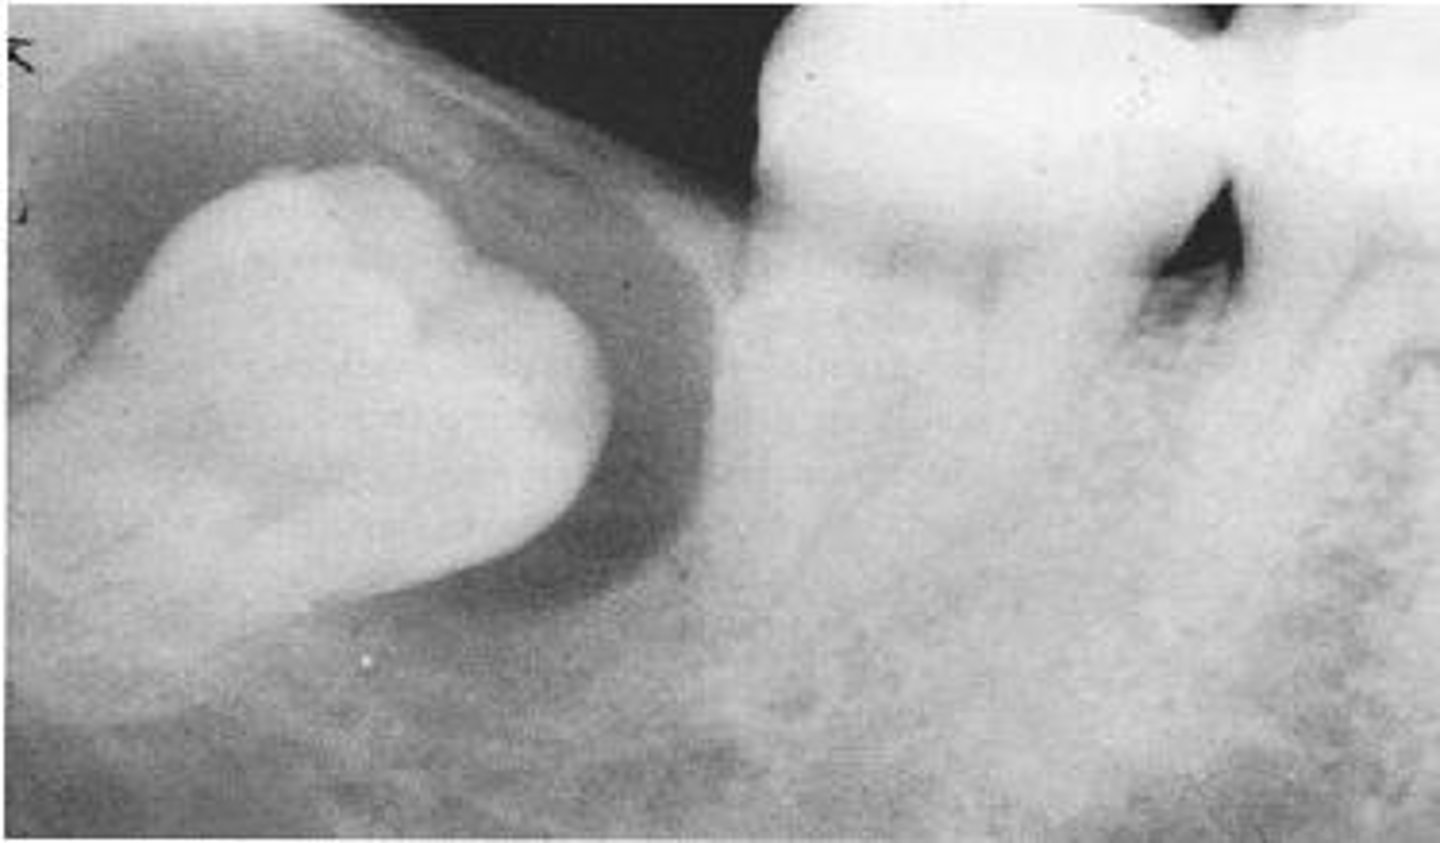

What type of cyst is a Dentigerous Cyst?

Odontogenic, non-inflammatory

Where are Dentigerous Cysts typically found?

Coronal to tooth

What is the second most common cyst type?

Dentigerous Cyst

What is a differential diagnosis for Dentigerous Cysts?

Ameloblastic fibroma